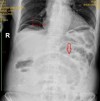

Vai trò của xquang bụng đứng trong chẩn đoán tổn thương tạng rỗng sau các phẫu thuật vùng bụng